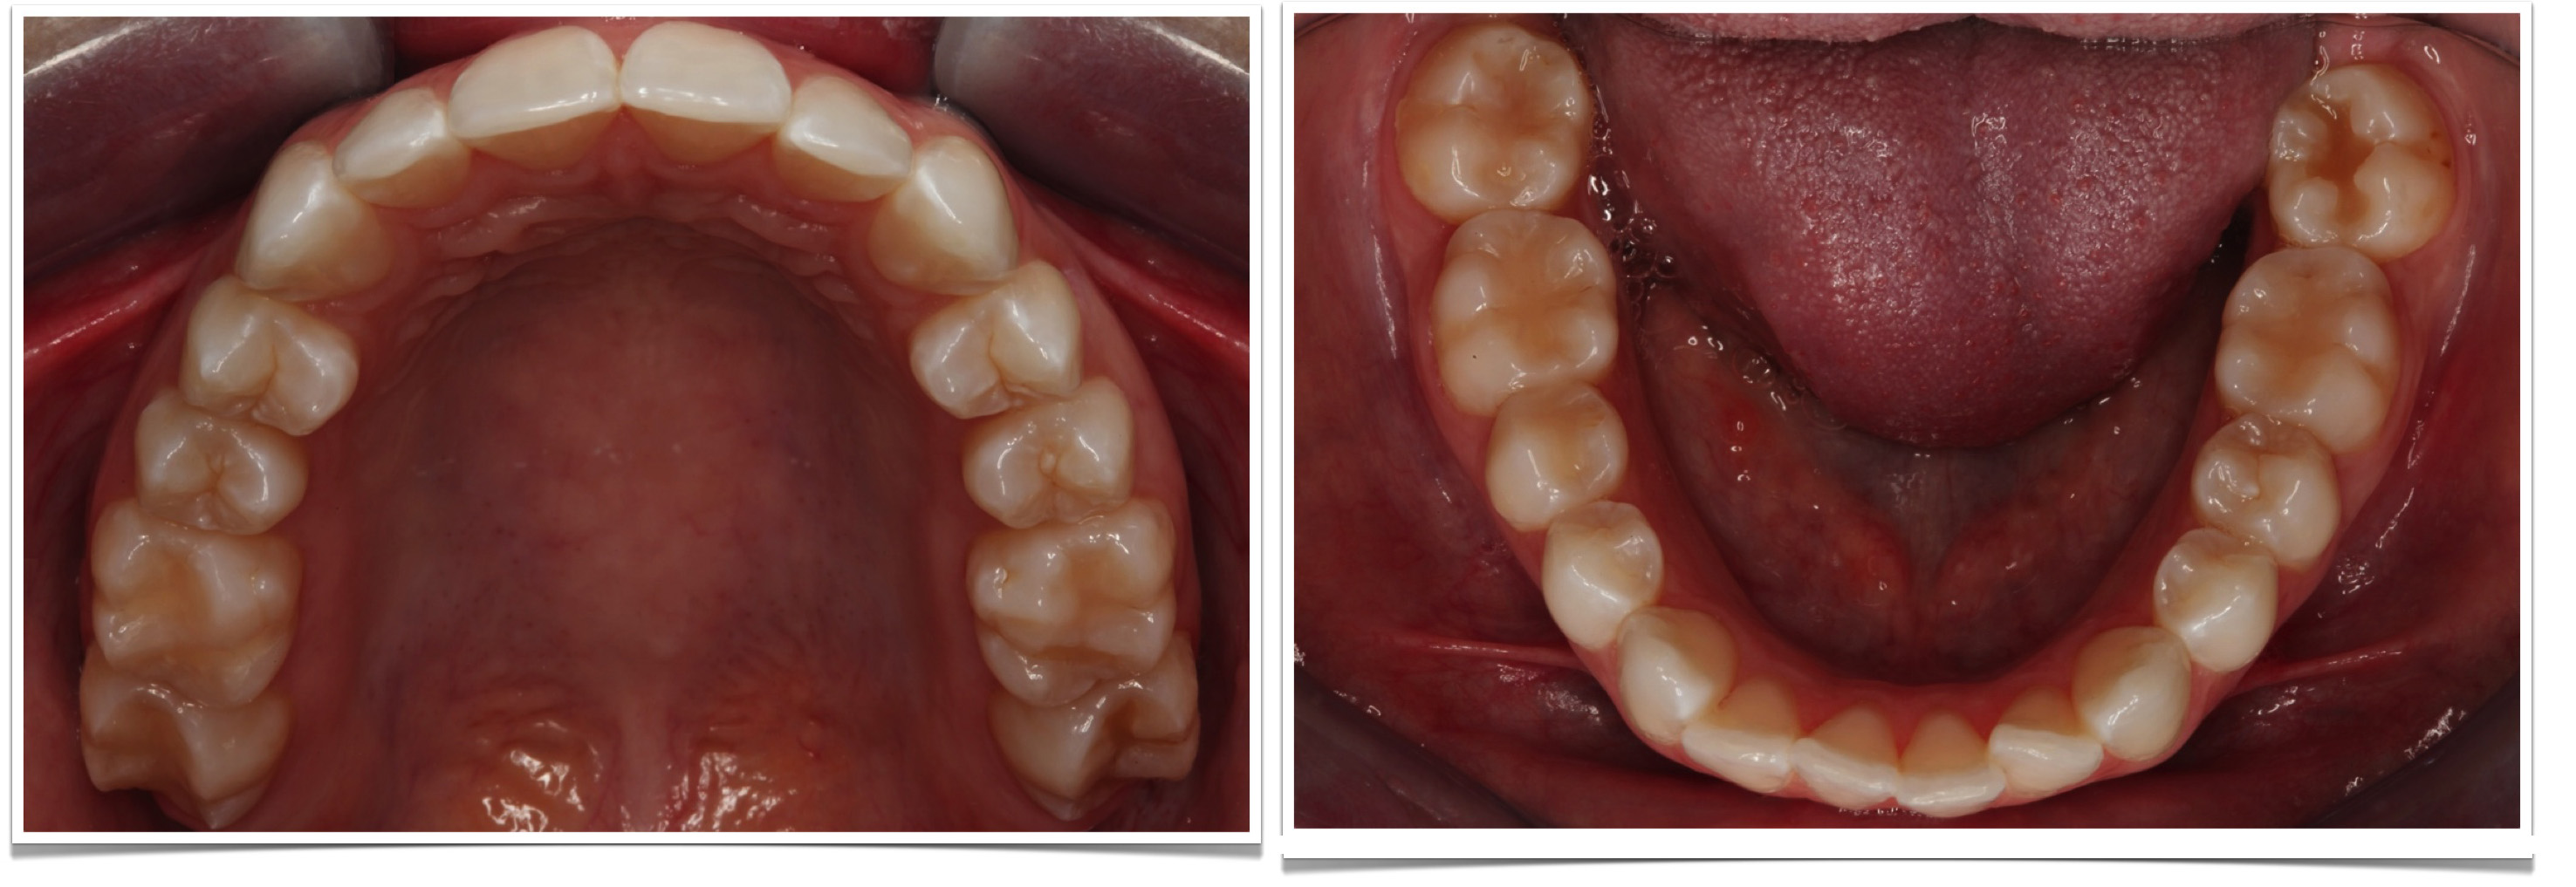

Final Intra-oral Photos. | Download Scientific Diagram

www.researchgate.netFrontal Intraoral Photo - Orthodontist St. George Utah | Burke

Final Intra-oral Photographs. | Download Scientific Diagram

www.researchgate.netIntraoral Dental Photography 5 – DentalProMaster